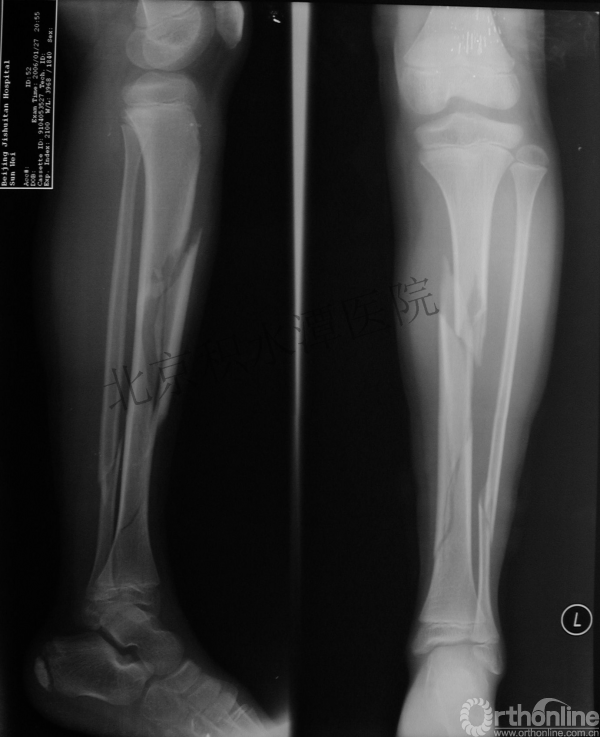

女孩、6岁,股骨干骨折

原始损伤

牵引后4周

伤后18月

没有任何外观和功能障碍!相信每位小儿骨科医生都会有很多类似的病例!除非您不承认或者没有认识到塑形!